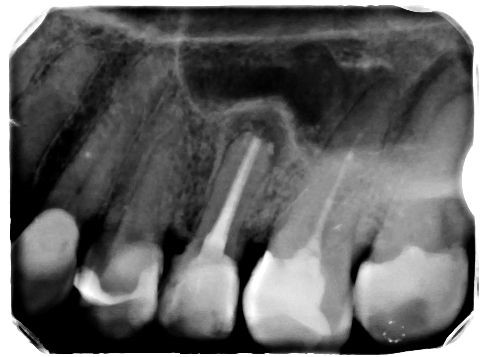

IV. Złamane narzędzie kanałowe

Złamane narzędzia są jednym z powikłań, które mogą wystąpić podczas leczenia kanałowego. Dzięki zastosowaniu odpowiedniego instrumentarium można jednak w wielu przypadkach usunąć złamany fragment narzędzia z kanału i doprowadzić do ostatecznego sukcesu terapii endodontycznej (ryc. 12‑14). Gdy narzędzia nie uda się usunąć, można spróbować wykonać zabieg jego obejścia, tak zwany bypass, a następnie szczelnie wypełnić kanał korzeniowy. Podczas całej procedury opracowania należy obficie płukać kanał, najlepiej stosując również aktywację za pomocą urządzeń dźwiękowych lub ultradźwiękowych. Jeśli do złamania narzędzia doszło jakiś czas temu, kanał jest prawidłowo wypełniony, a ząb asymptomatyczny i nie wymaga nowej odbudowy, można wstrzymać się od ingerencji stomatologicznej, ale koniecznie obserwować ząb zarówno w badaniu klinicznym, jak i radiologicznym. Sam fakt obecności złamanego narzędzia w jamie zęba nie kwalifikuje go od razu do powtórnego leczenia kanałowego, a już na pewno nie do ekstrakcji.

Ryc. 12. Zdjęcie rentgenowskie zęba 25 wykonane przed podjęciem leczenia w specjalistycznej poradni endodontycznej – widoczne złamane narzędzie w kanale korzeniowym.

Źródło: Olczak K. Złamane narzędzia kanałowe – powikłanie w endodoncji, z którym można sobie poradzić. Mag Stomatol. 2019; 9: 13.

Ryc. 13. Zdjęcie rentgenowskie zęba 25 wykonane po usunięciu narzędzia.

Źródło: Olczak K. Złamane narzędzia kanałowe – powikłanie w endodoncji, z którym można sobie poradzić. Mag Stomatol. 2019; 12: 13.

Ryc. 14. Zdjęcie rentgenowskie zęba 25 wykonane po wypełnieniu kanałów korzeniowych.

Oczywiście decyzja co do przyszłości zęba ze złamanym narzędziem jest uzależniona od:

- momentu, w którym doszło do złamania narzędzia,

- jakości wypełnienia kanału,

- stanu tkanek okołowierzchołkowych,

- ogólnego zdrowia pacjenta,

- całościowego planu leczenia (25, 26).